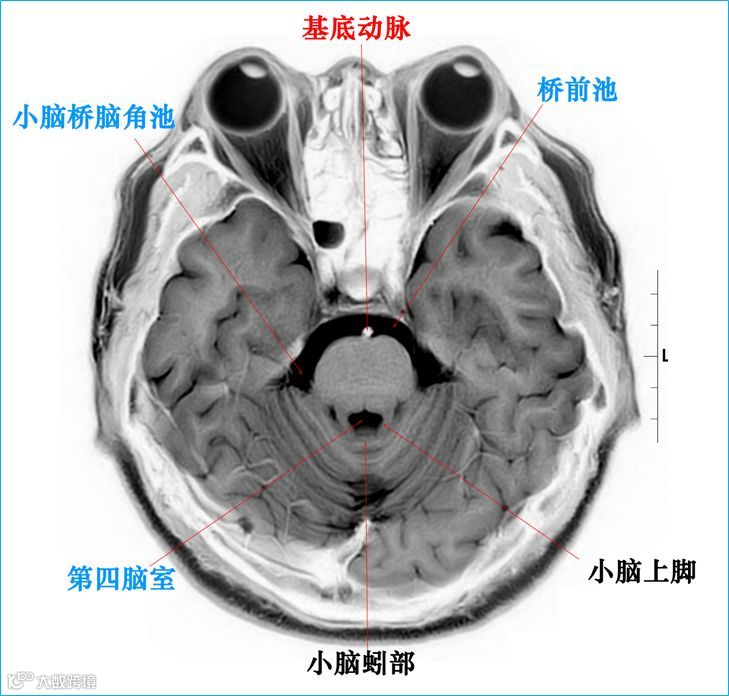

在T2WI反相图学下的颅脑断层解剖(吴晓安老师亲自手动标准)以及标本断层解剖,满满干货,坐在小板凳上,一起学习吧……